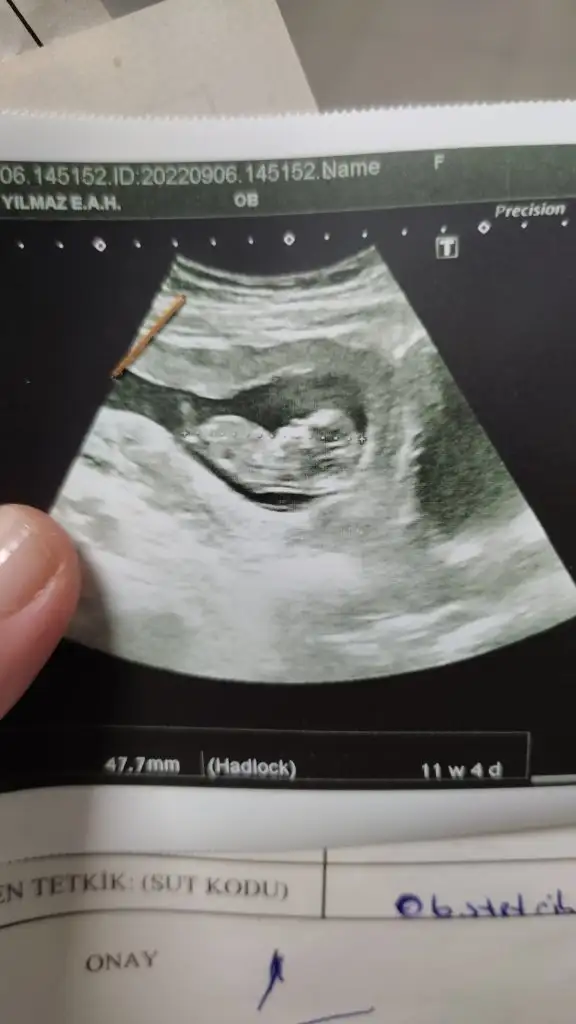

Canım sanki değer yüksek değil gibi geldi internetten de baktım da onların referans değer farklı mı acaba doktorun varmı takipli olduğunKızlar sonuçlar bu şekilde şuan doktoru bekliyorum inşallah iyi şeyler duyarım ikili test cut of üzerinde diyor ve korkuyorum üzüldüm Bi anda

Ya bnde tam anlamam ama 1.250 gösteriyo en yuksek sınır stres yapma canim hem kesin sonuc bile olmuyo. Ense burun iyiyse sıkıntı olacağını sanmam. Insallah dr pozitif bi dr dur. Psikolojiyi cok etkiliyoKızlar sonuçlar bu şekilde şuan doktoru bekliyorum inşallah iyi şeyler duyarım ikili test cut of üzerinde diyor ve korkuyorum üzüldüm Bi anda